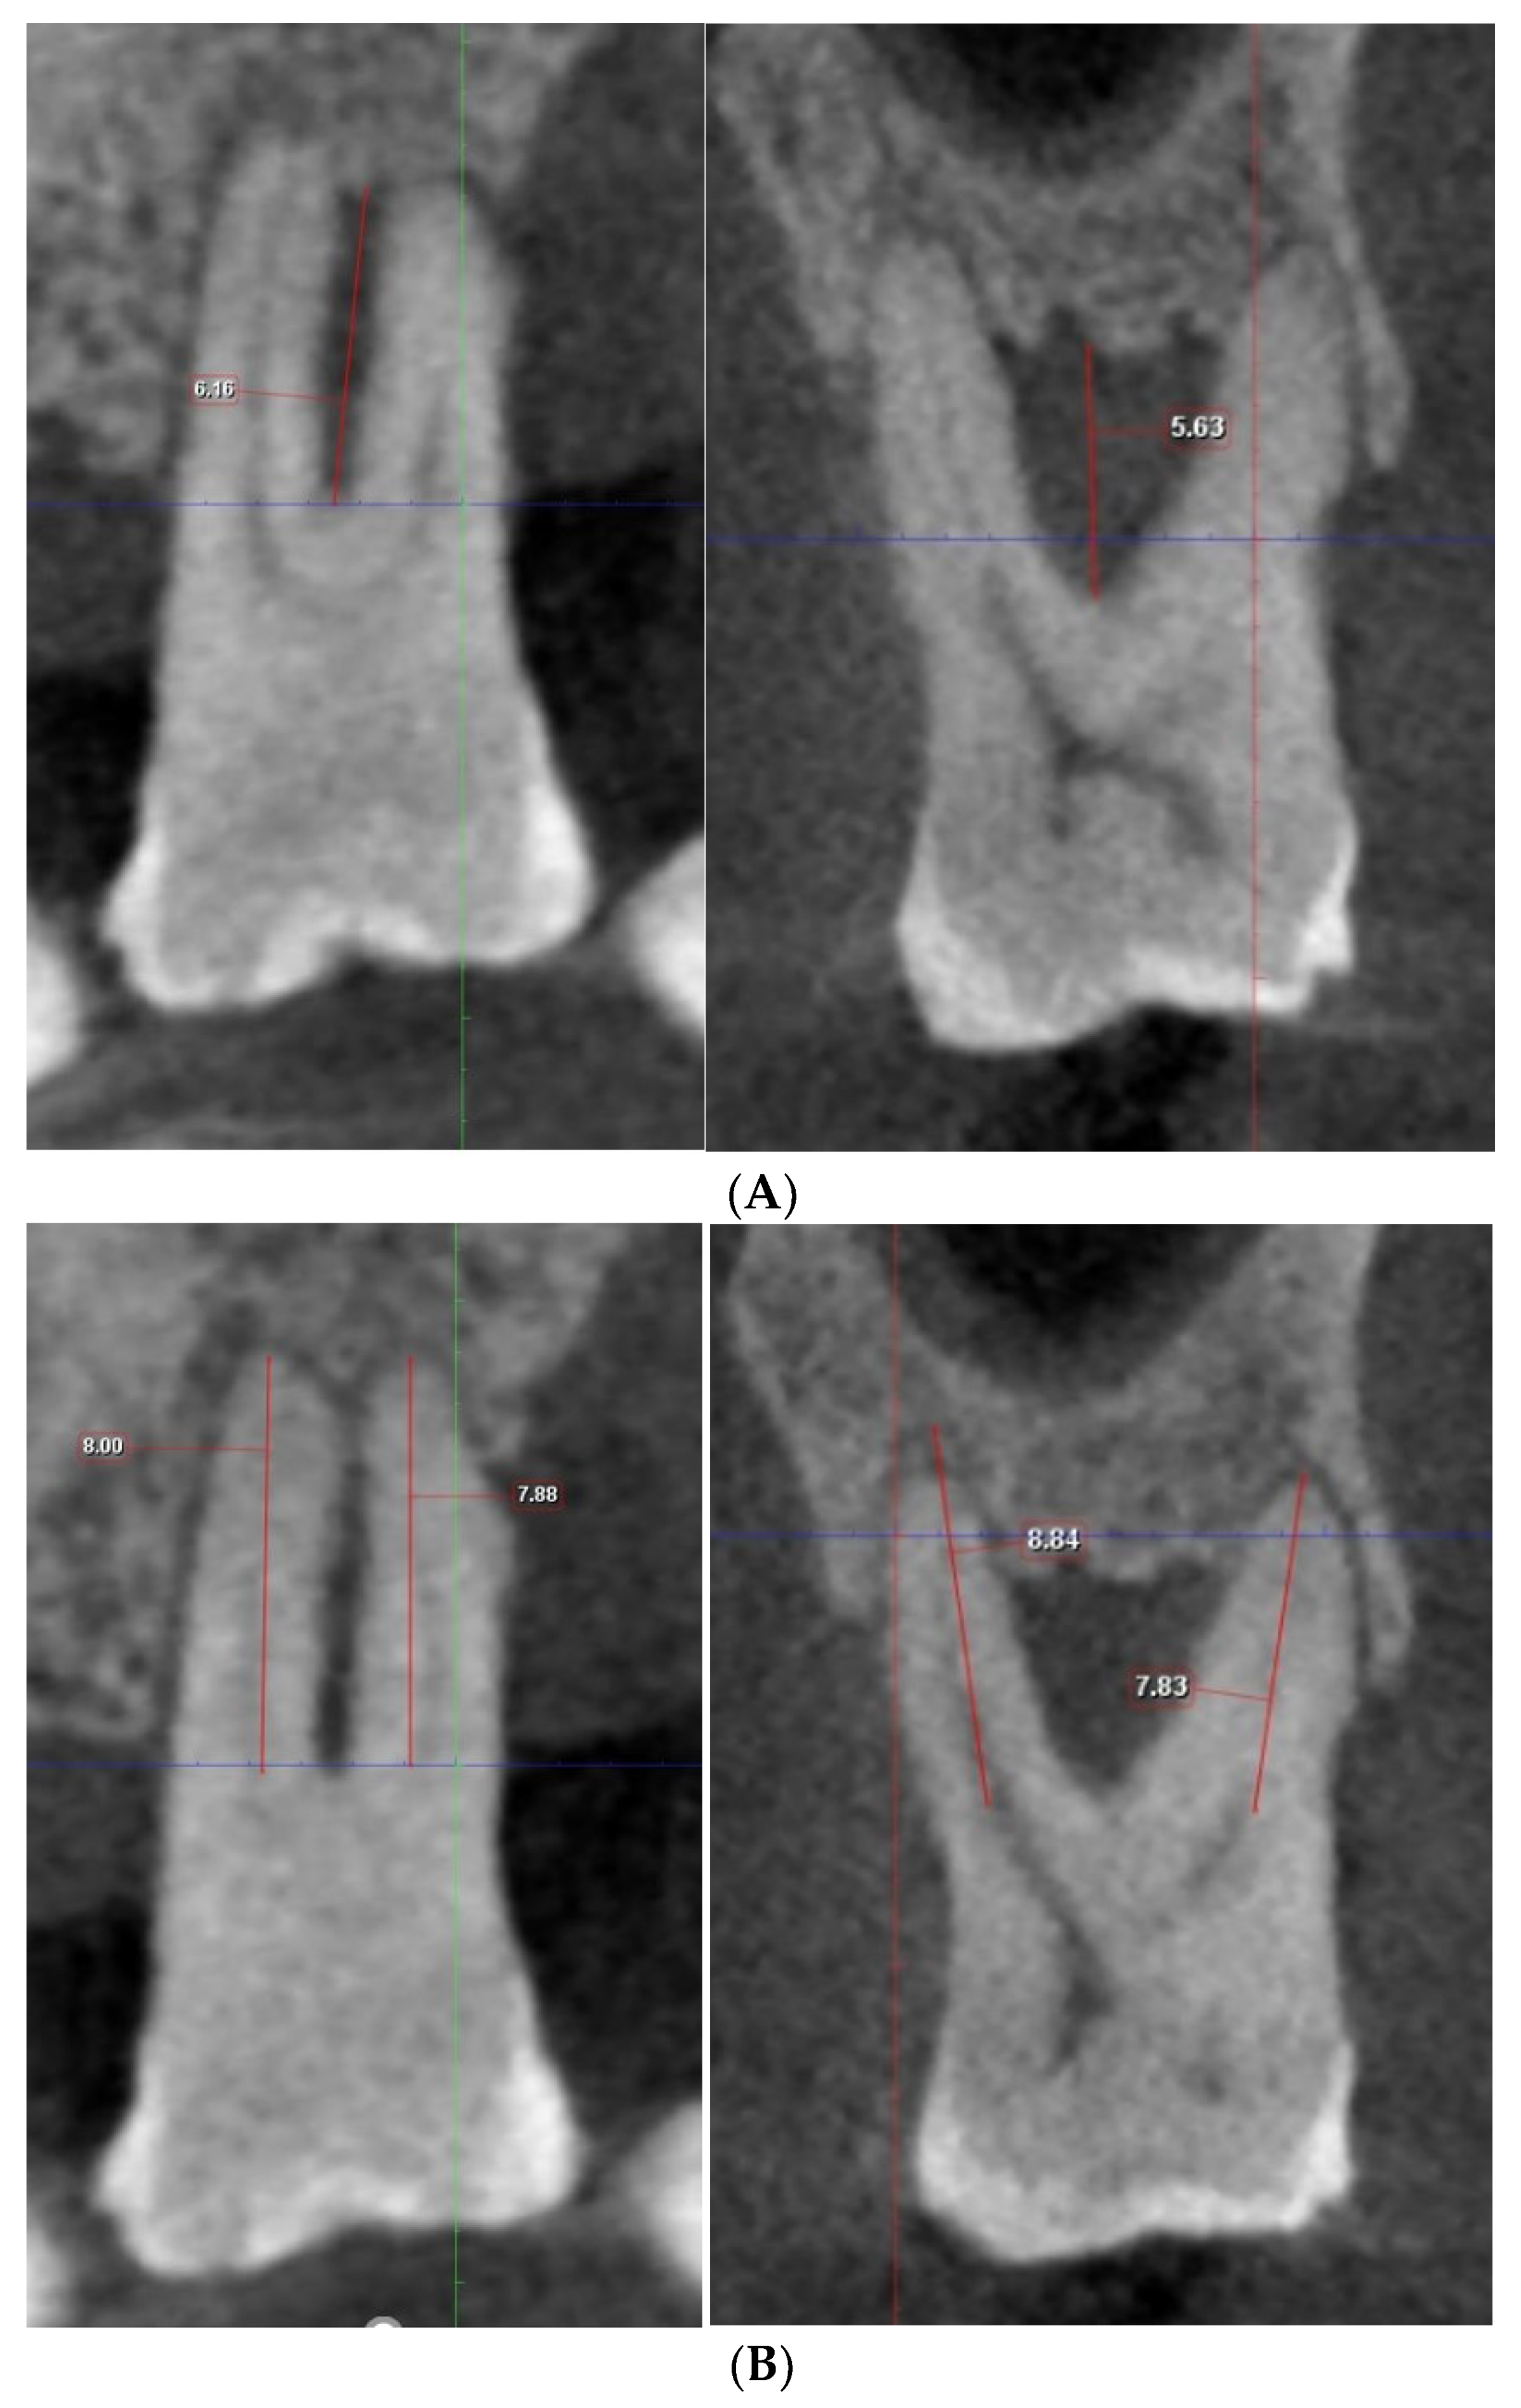

2.4. Gold Standard Assessment

2.5. Examiners and Image Analysis